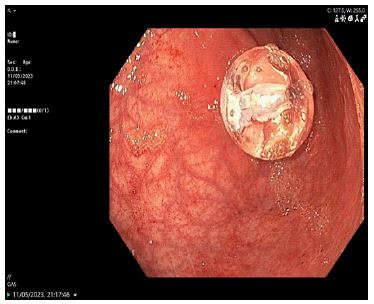

A temporary Foley catheter secured the tract. Subsequent endoscopy did not visualize the tube in the duodenum but found the gastrostomy device within the stomach (Figure 1). A new 14F replacement tube was inserted. The duodenal component seen on CT was presumed likely to pass spontaneously (Figure 2), and the patient was monitored for obstruction.

Figure 1: Endoscopic examination, only the balloon portion of the gastrostomy tube is visible at the insertion site, with the external tube itself no longer in place.